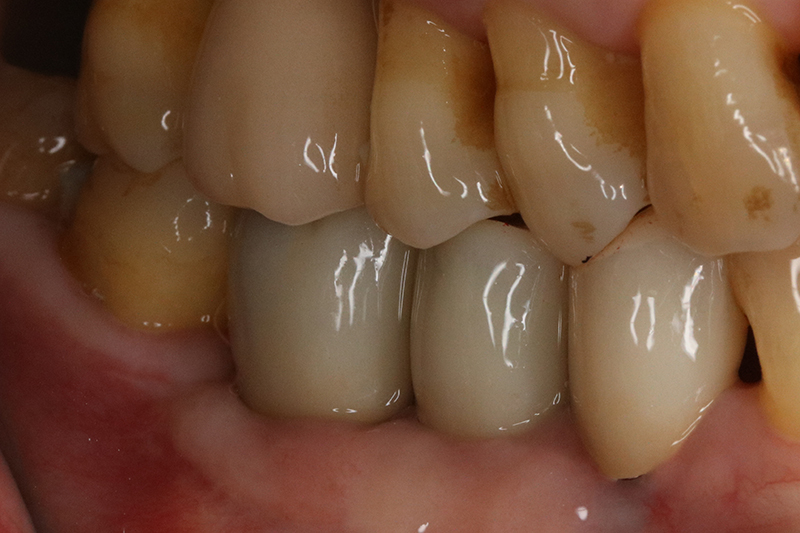

缺牙多顆

案例二

術後